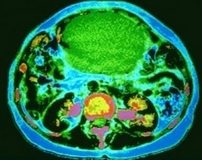

Over kanserlerinde tedavi başarısı açısından ilk etapta cerrahi müdahale çok önemlidir.

Operasyon sonrasında tedaviye kemoterapiyle devam ediliyor.

Standart tedavi olarak karboplatin ve paklitaksel uygulanmakta; fakat relaps durumunda karboplatin artı lipozomal doksorubisin tedavisine geçiliyor.